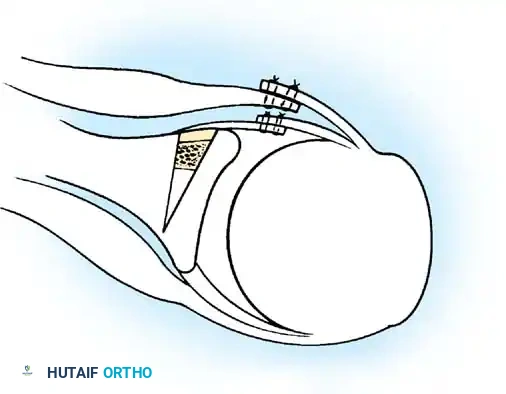

- Anchor Placement: Suture anchors (typically 3 to 4) are placed along the articular margin of the anteroinferior glenoid (from the 5:30 to 3:00 positions for a right shoulder). Anchors must be inserted at a 45-degree angle to the articular surface to maximize pullout strength and avoid joint penetration.

Capsular Shift and Closure

To address capsular redundancy, an inferior capsular shift is performed.

- The arm is positioned in 30 to 45 degrees of abduction and 20 degrees of external rotation.

- The inferior capsular flap is advanced superiorly and laterally, tensioning the IGHL complex. The sutures from the anchors are passed through the shifted capsule and tied.

- The superior flap is then brought down over the inferior flap in a "pants-over-vest" fashion to reinforce the anterior wall and close the rotator interval.